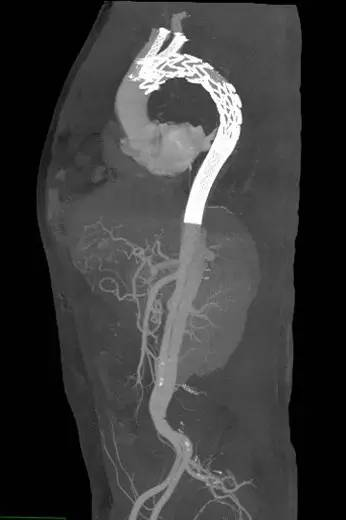

手术过程非常顺利,王兵副院长亲自操刀,整个手术过程仅耗时2小时。术后在施敏护士长带领的护理团队精心的护理下,患者恢复良好,术后复查CTA(见下图),主动脉支架位置良好,破口封堵满意,无内漏,两个“烟囱”支架通畅,无脑梗塞、肢体及内脏缺血等并发症的发生。现在大家悬着的心完全放了下来,叮嘱患者一定要控制血压,按时随访,复查CTA评估支架的情况。

主动脉、左颈总动脉及左侧锁骨下动脉支架

术后复查CTA

1周、2周、1个月,随着时间的推移,通过药物治疗,病人的情况逐渐趋于稳定,大家紧悬的心也都稍稍的放下了一些,而每次复查CTA也都让大家看到了希望。升主动脉及主动脉弓部的血肿逐渐吸收减少,终于在1个半月的时候再次复查CTA,血肿基本吸收完全,有了腔内治疗的条件!因为破口位置紧贴左侧锁骨下动脉,为获得足够的锚定区,支架近端必须覆盖左侧锁骨下动脉及左侧颈总动脉,上述动脉一旦覆盖将导致脑梗塞、上肢动脉缺血等严重并发症!针对这种情况,王兵副院长果断提出使用完全微创的“烟囱”技术完成此次手术。

所谓的“烟囱”技术,就是在植入主动脉覆膜支架之前,经左侧肱动脉及左侧颈总动脉穿刺后分别预留导丝,待主动脉支架释放后,再经预留导丝分别置入支架,供应上面两个动脉的血供,从而避免脑梗塞、肢体缺血等严重并发症,因外观像烟囱,故形象的称为“烟囱”技术。